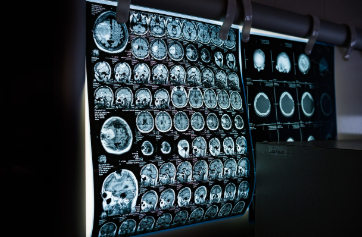

조영제는 영상 검사 시 우리 몸속 특정 부위나 혈관을 더 잘 보이도록 만드는 약물입니다. 쉽게 말해, 사진을 찍을 때 그림자를 없애고 빛을 더해 사물의 윤곽을 뚜렷하게 만드는 것과 같다고 할 수 있습니다. 이 약물을 정맥에 주입하면 혈관을 타고 순환하면서 병변의 특징을 명확히 보여주어 의료진이 정확한 진단을 내리는 데 도움을 줍니다. 조영제 덕분에 종양의 크기나 위치, 혈관의 협착 여부 등 맨눈으로는 보기 힘든 정보를 얻을 수 있습니다.

CT와 MRI는 검사 원리가 다르므로, 각각의 원리에 맞게 특화된 조영제를 사용합니다.